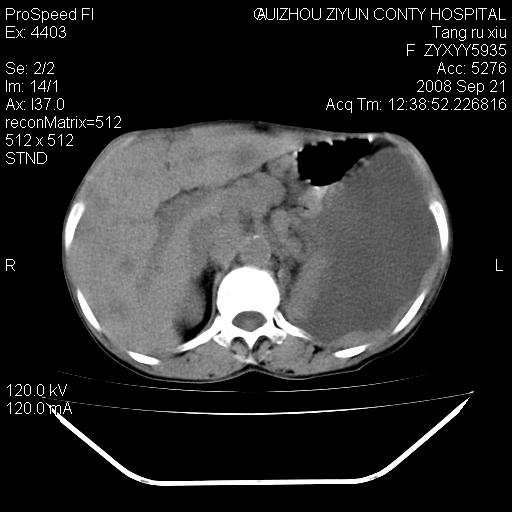

肝脏大小形态尚可,其实质内可见多发大小不等的低密度影,边缘模糊。肝门区结构紊乱,腔静脉腹主动脉旁可见多发软组织密度影,部分融合成团块状,并向下延伸。胰腺及十二指肠结构显示不清。腹腔内脐后肠管走形僵硬,管壁可见增厚。盆腔内可见多个淋巴结影。所扫层面左侧胸腔可见大量弧形水样密度影,其内侧可见被压缩的肺组织影。左侧胸壁可见一小结节样软组织密度影,边缘模糊。心脏纵隔向右侧移位。心脏包膜内可见囊样低密度影,其内侧心房室周围可见一圈气体样密度影。纵隔内大血管旁可见多发软组织团块影,部分融合。

1.腹膜后淋巴瘤侵及肝脏,肺内及纵隔内多发转移。2.左侧大量胸腔积液并压缩性肺不张。3.心包脓肿可能,转移不除外。4.脐后局部肠管管壁增厚,考虑炎症可能,肿瘤不除外。

为什么没有人注意到腹腔脐后的那段肠管呢?那段看着很不好的样子。

左侧中心型肺癌并胸膜及心包转移。肝内转移,腹膜后淋巴结转移。